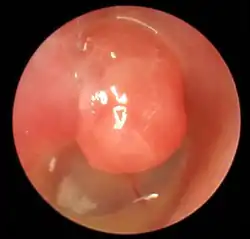

Kongenitales Cholesteatom

Das seltene kongenitale Cholesteatom entsteht aus Zellversprengungen während der Embryonalphase, genauer gesagt durch nicht vollständig zurückgebildetes mesenchymales Gewebe in der Submukosa des Mittelohres. Im Gegensatz zu den anderen Cholesteatomen entwickelt sich das kongenitale Cholesteatom hinter intaktem Trommelfell und (zumindest primär) ohne Kontakt zum Trommelfell.[20]

Die Diagnose wird mit Hilfe der Ohrmikroskopie gestellt. Der typische Befund ist ein Defekt in der Pars tensa oder Pars flaccida des Trommelfells mit Nachweis weißlich-gelber Schuppen oder Zellmassen in der Läsion. Nicht selten finden sich Polypen aus Granulationsgewebe. Untersucht man das Trommelfell durch die direkte Otoskopie, sieht man häufig eine Perforation des Trommelfells am oberen oder hinteren Rand.